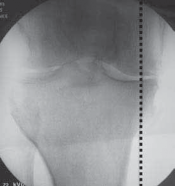

TECH FIG 4•A.

Fluoroscopic image showing the thin osteotomes completing the osteotomy cut to within 1 cm of the lateral cortex.

Single black arrow,

osteotomy guide pins;

double black arrows

, osteotome;

, posterior retractor protecting the neurovascular structures.